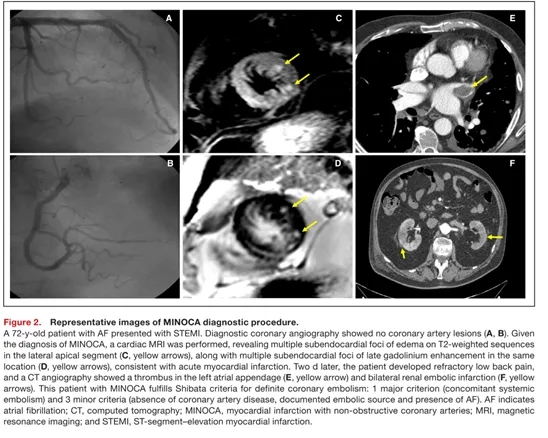

STEMI和非STEMI根据当前欧洲心脏病学会(ESC)指南定义。如果存在动脉粥样硬化血栓、冠状动脉扩张、斑块破裂或侵蚀(腔内影像学检查)、自发性冠状动脉夹层、血管痉挛或应激性心肌病的证据,则排除患者。在非阻塞性冠状动脉心肌梗死(MINOCA)病例中,当心脏磁共振(CMR)显示与局灶性急性缺血性损伤一致的表现——特征为心内膜下或透壁性延迟钆增强伴相应局灶性心肌水肿——且同时符合Shibata标准时,支持CE诊断(图2)。

初始诊断为MINOCA的患者按照当前指南进行了心脏磁共振检查(图2)。检查包括长轴和短轴电影稳态自由进动序列,用于评估心室功能和室壁运动异常;T2加权短tau反转恢复序列检测心肌水肿;以及静脉注射钆对比剂后10-15分钟的延迟钆增强成像,使用相位敏感反转恢复序列识别心肌坏死或纤维化。反转时间个体化调整以达到正常心肌最佳信号抑制。如果存在≥1个急性缺血灶——在T2加权黑血序列上识别为水肿,并在相同位置有心内膜下或透壁性延迟钆增强——则由2名专家重新评估冠状动脉造影。如果影像学发现可疑特征或提示CE以外的其他原因(如斑块侵蚀、自发性冠状动脉夹层等),则排除患者。CE诊断的观察者间Kappa一致性为0.89。